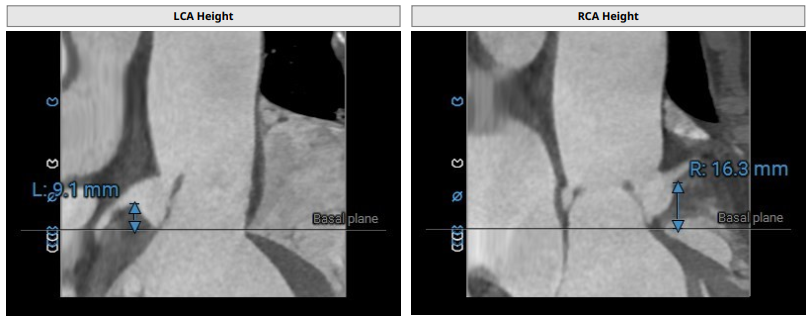

术前影像评估提示,患者主动脉瓣为三叶瓣结构,瓣叶基本等大,左右瓣稍有粘连,瓣叶中度增厚,游离缘轻微钙化。主动脉瓣环直径31.0mm,左心室流出道直径36.4mm,STJ直径33.8mm,升主动脉直径38.8mm,左冠脉开口高度偏低(9.1 mm),左冠瓣瓣叶长约19.4mm,存在术中冠脉阻塞潜在风险,右冠脉开口高度充足,瓣叶长约18.0mm,左室与主动脉夹角161°,心脏角度60°。

CTA评估(上下滑动查看更多照片)

瓣膜选型:JS/TAVI-31瓣膜